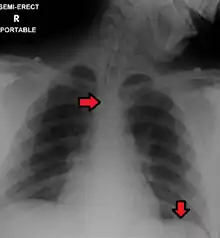

Great care must be taken to ensure that the tube has not passed through the larynx into the trachea and down into the bronchi. The reliable method is to aspirate some fluid from the tube with a syringe. This fluid is then tested with pH paper (note not litmus paper) to determine the acidity of the fluid. If the pH is 4 or below then the tube is in the correct position. If this is not possible then correct verification of tube position is obtained with an X-ray of the chest/abdomen. This is the most reliable means of ensuring proper placement of an NG tube.[11] The use of a chest x-ray to confirm position is the expected standard in the UK, with Dr/ physician review and confirmation. Future techniques may include measuring the concentration of enzymes such as trypsin, pepsin, and bilirubin to confirm the correct placement of the NG tube. As enzyme testing becomes more practical, allowing measurements to be taken quickly and cheaply at the bedside, this technique may be used in combination with pH testing as an effective, less harmful replacement of X-ray confirmation.[12] If the tube is to remain in place then a tube position check is recommended before each feed and at least once per day.